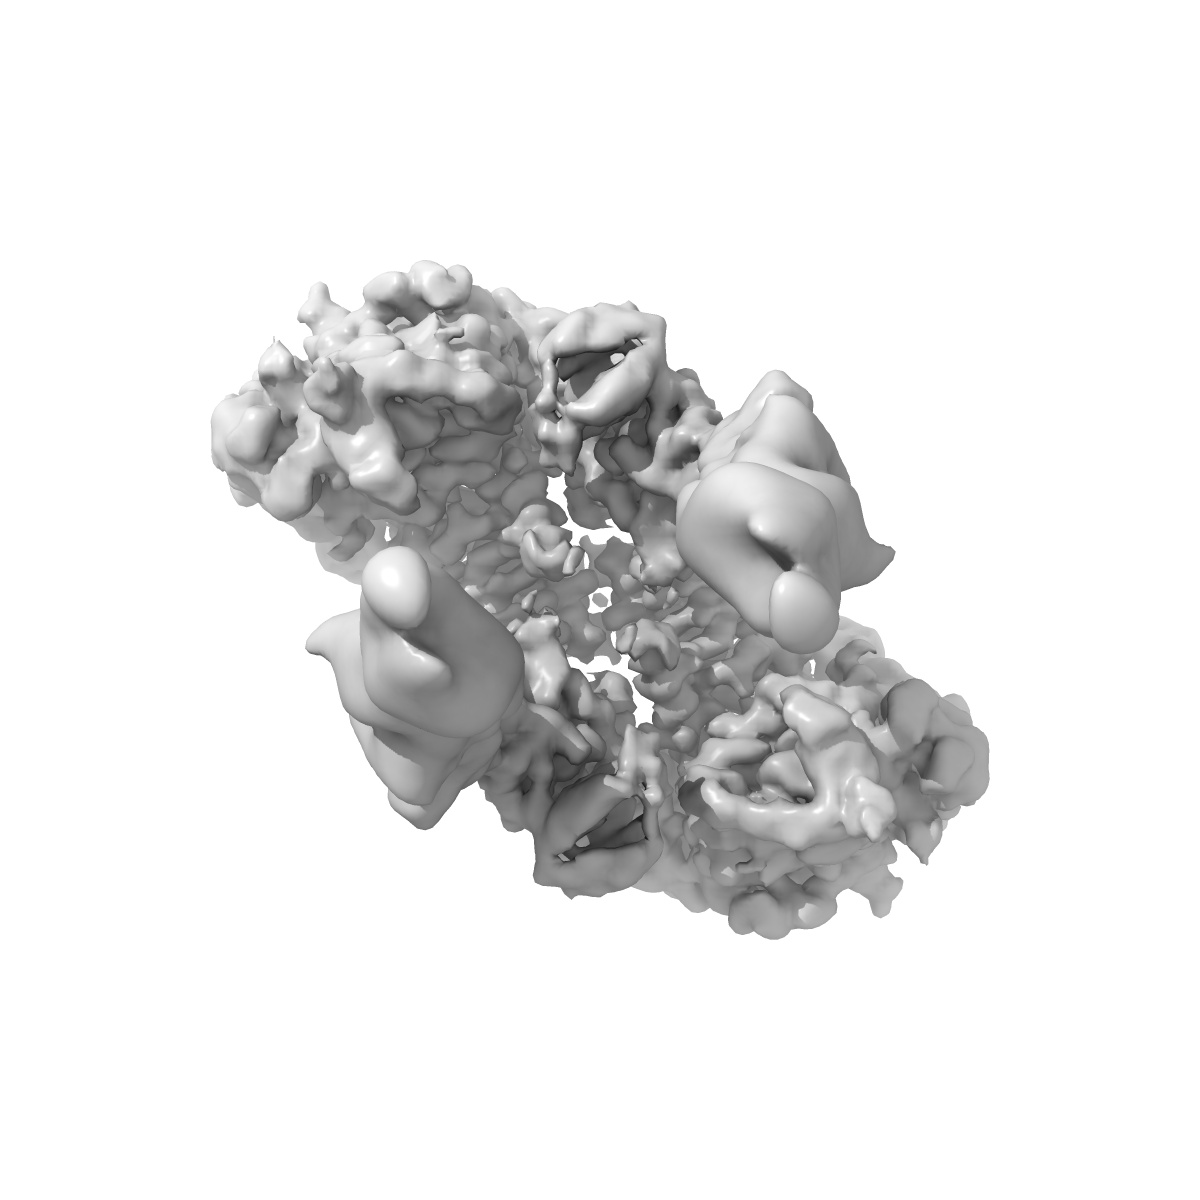

Cryo-EM structure of long form insulin receptor (IR-B) with four IGF2 bound, symmetric conformation.

Single-particle3.6 Å

Sample: Long form insulin receptor (IR-B) with four IGF2 bound, symmetric conformation.